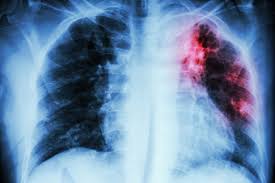

Tuberculose pulmonaire Solution naturelle: La tuberculose pulmonaire est une infection bactérienne causée par Mycobacterium tuberculosis, qui affecte principalement les poumons. C’est une maladie contagieuse qui se transmet par les gouttelettes respiratoires. Tuberculose pulmonaire Solution naturelle par les Plantes

Symptômes courants

- Toux persistante (plus de 3 semaines), souvent avec crachats parfois sanglants

- Essoufflement et douleur thoracique